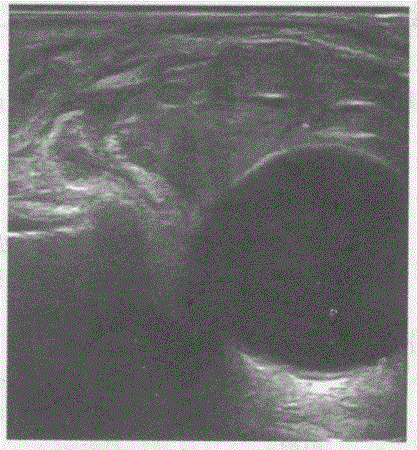

判断下图、彩图符合哪种眼睑疾病:{图1}超声提示:A.眼睑神经纤维瘤B.眼睑皮样囊肿C.眼睑血肿D.睑板腺癌

选项 A.眼睑神经纤维瘤 B.眼睑皮样囊肿 C.眼睑血肿 D.睑板腺癌

答案 A